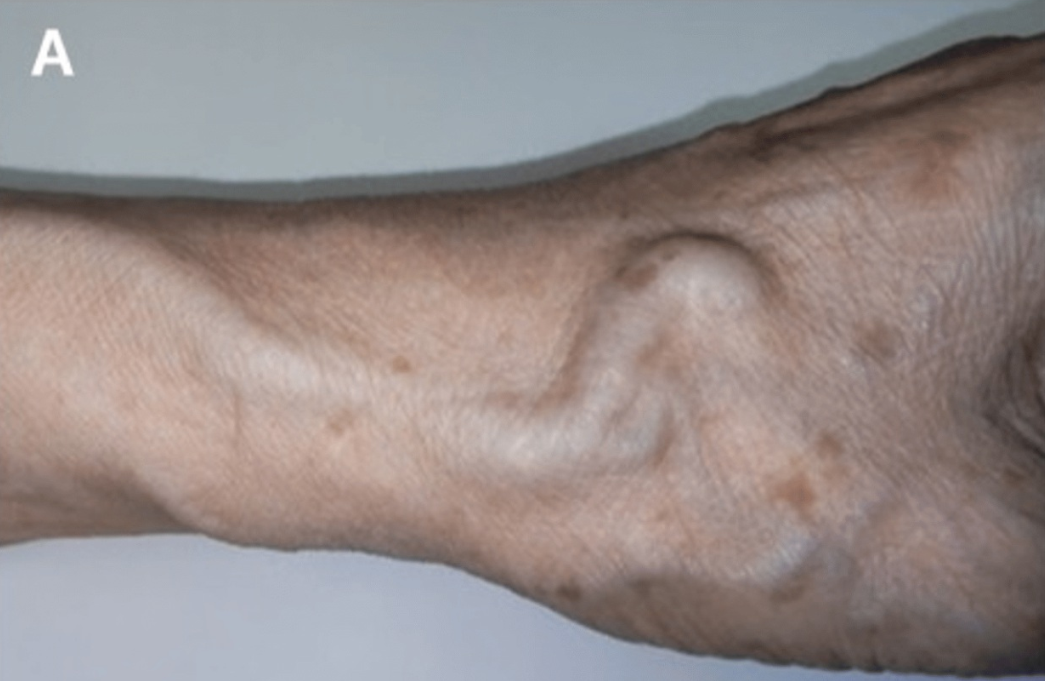

三年后,他因外周动脉疾病伴间歇性跛行,接受了冠状动脉造影和下肢动脉造影。造影前,触诊桡动脉能感觉到震颤。此外,还观察到如图1A所示的扩张的头静脉。

图1.dTRA形成动静脉瘘的照片、超声表现和血管造影图像。

(A)观察到扩张的头静脉。(B)箭头显示动静脉瘘的入口,即桡动脉与静脉连接处。浅表超声检查发现远端桡动脉有一个直径为2.0mm、流速为3.75m/s的动静脉瘘。(C)桡动脉造影。显示远端桡动脉与手背静脉网之间存在分流,并且头静脉和贵要静脉显影。分流位于桡动脉至靠近拇指掌骨的静脉处。(D)常见的远端桡动脉穿刺部位(三角形)和本例的穿刺部位(星形)。